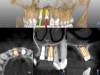

Plan-The image data in Digital Imaging Communication in Medicine (DICOM) format is imported to the navigation system by a direct transfer using the local network. Registration of the fiducial image in the CT scan is performed (automatically) and verified by the user at this point. STL files of either the dentition or prosthetic wax-ups can be imported from optical scanning for prosthetically directed treatment planning (Figure 4). Virtual teeth are placed and adjusted to simulate the desired restoration, and supporting implants are placed in consideration of the prosthetic plan. While considerable time is spent in the planning phase, the surgeon has the opportunity to modify the plan during the operation if the surgical environment warrants change.

The surgery was performed under local-regional anesthesia. The thermoplastic retainer was placed over the remaining teeth and its fit/stability verified. Atraumatic extractions of teeth Nos. 8 and 9 were performed, and intact buccal bone was verified. Osteotomy site preparation and immediate implant placement were performed using the dynamic surgical navigation system. Two 3.6 mm x 9 mm implant fixtures (Astra Tech EV, Dentsply Sirona, dentsplysirona.com) were placed. SmartPegs (Osstell, osstell.com) were attached to the implants to show the trajectory of the fixture positioning. After implant placement, anorganic bovine bone matrix (Bio-Oss®, Geistlich Pharma, geistlich-na.com) was used to graft the implant alveolus "gap," and healing abutments were placed (Figure 9 and Figure 10). The patient was provided with an interim removable appliance for tooth replacement.

A post-placement CBCT scan was secured and compared to the preoperative CBCT plan using software inherent to the dynamic navigation system (Figure 11). Accuracy results from this case (preoperative plan compared to post-implant placement) were as follows: entry point deviation was 0.13 mm for tooth position No. 8 and 0.41 mm for No. 9; angle discrepancy was 4.3 degrees for No. 8 and 6.76 degrees for No. 9; implant apex depth deviation was 1.10 mm for No. 8 and 1.37 mm for No. 9.